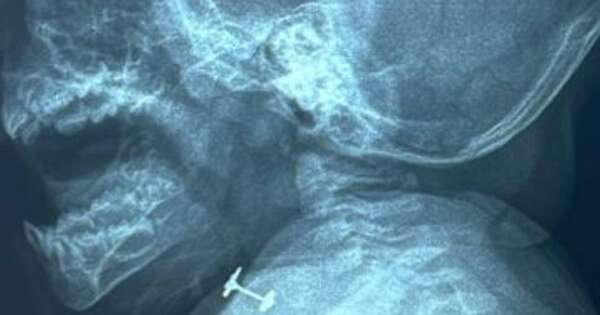

La Nación / Bebé de diez meses tragó un arito, pero ya está fuera de peligro

Una beba de diez meses fue intervenida de urgencia en el Instituto Nacional de Enfermedades Respiratorias y del Ambiente (Ineram) luego de tragarse un arito. La oportuna atención médica salvó a la familia de una tragedia y hoy la menor ya se encuentra fuera de peligro, según informó el doctor Carlos Morínigo. ...[Leer más]